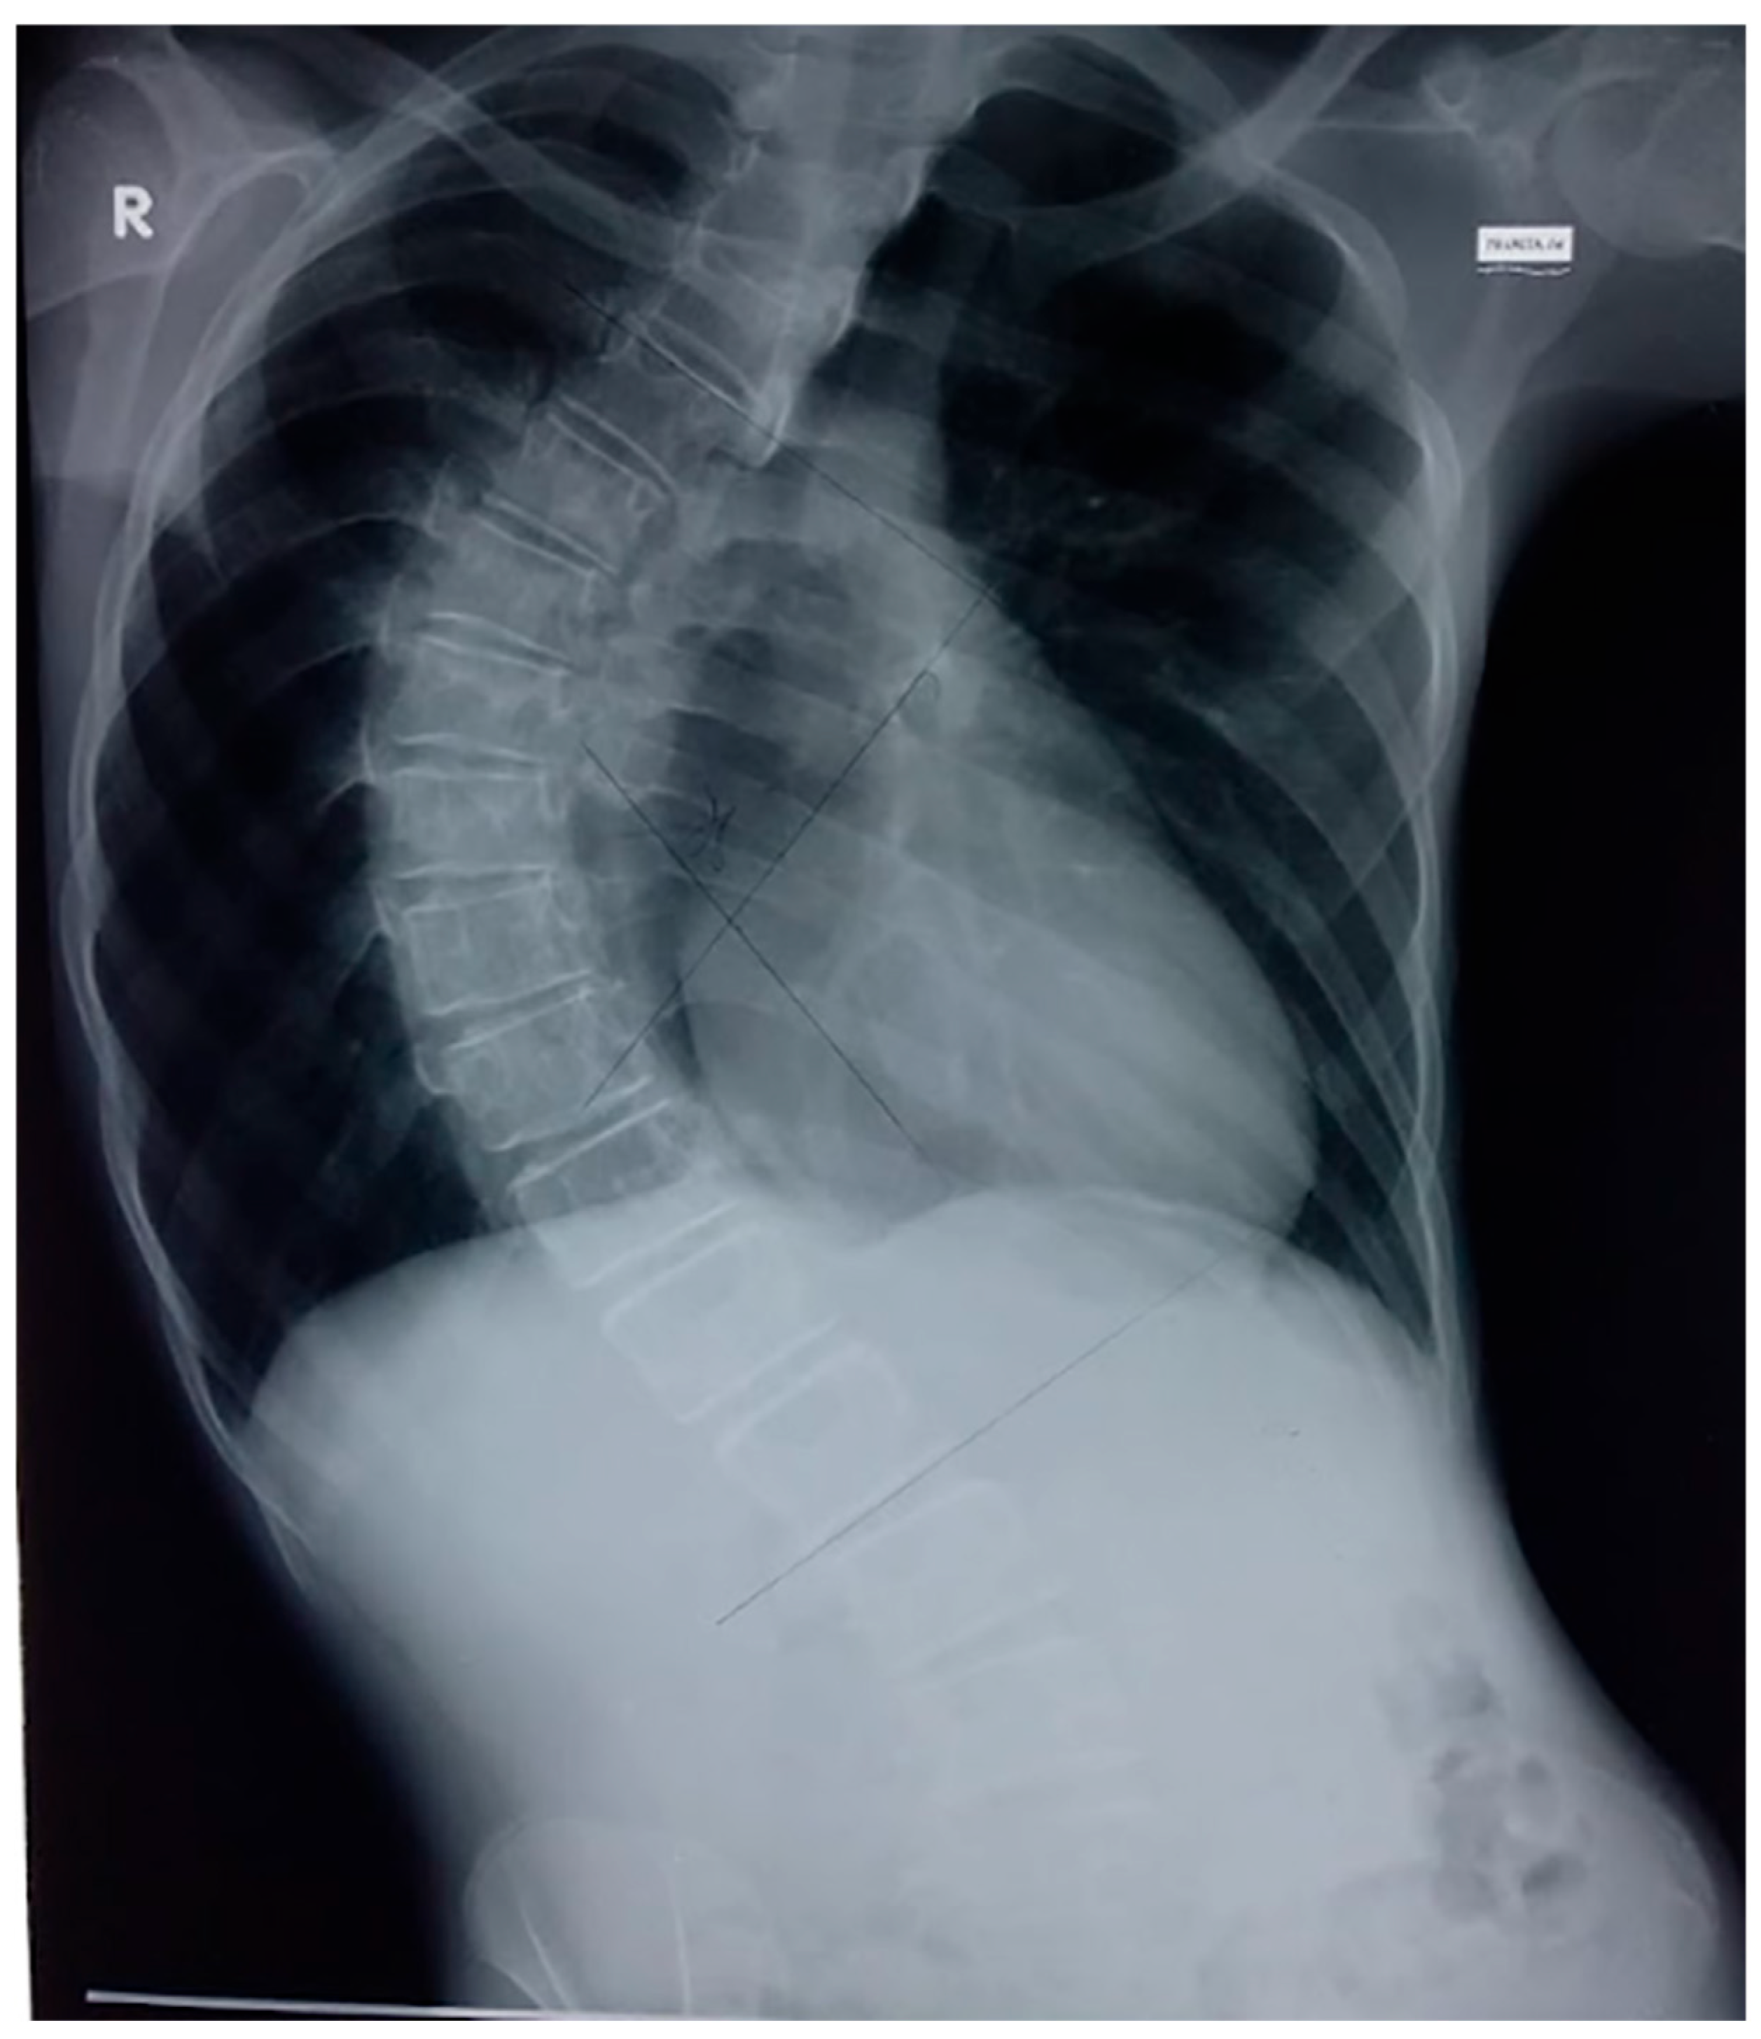

2. Case Presentation